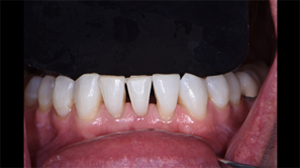

The patient is a male who presented with a chief concern of unesthetic black triangles in the upper anterior and lower anterior sextants. He had recently completed Invisalign treatment to address the black triangles and was disappointed that the orthodontic treatment didn’t resolve his esthetic concerns and in fact worsened the esthetic dilemma. He subsequently sought out a conservative solution for black triangle treatment.

The patient was congenitally missing tooth #26. The black triangles were moderately large in size. The challenge was to close the spaces and create anatomic tooth contours and widths and proper verticality of contact lengths.

Fig. 1: Pre-operative photo with contrast background to fully show the dimensions of the black triangles resulting from congenitally missing tooth #26 and adult orthodontic treatment.